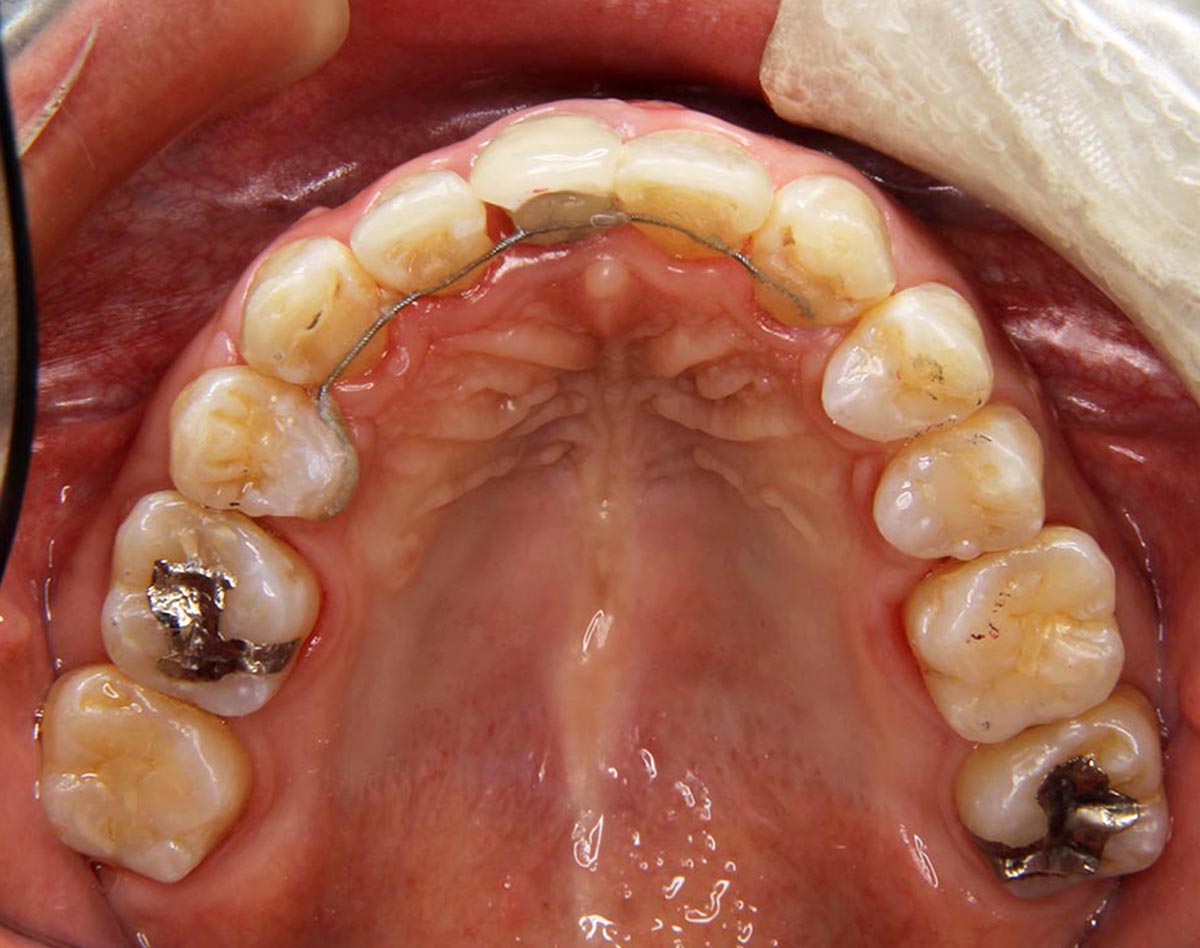

叢生(デコボコ)症例

●主訴

歯のデコボコが気になる

●診断

AngleⅠ級・前歯部叢生

●治療に用いた主な装置

上顎にリンガルブラケット矯正装置、下顎にマルチブラケット装置(ハーフリンガル)

●抜歯部位

非抜歯

●治療期間

2年10ヶ月

●治療費用

約108万円(ともに税込、調整費、保定費まで含む総額制)

●付記

歯列が狭かったので、拡大してから非抜歯で矯正しました。リスクとして、

①歯根吸収…今回は全くありませんでした。

②カリエス(むし歯)…今回は治療途中でむし歯治療を行いました。

③あともどり…保定装置の装着をしっかりしていただいています。